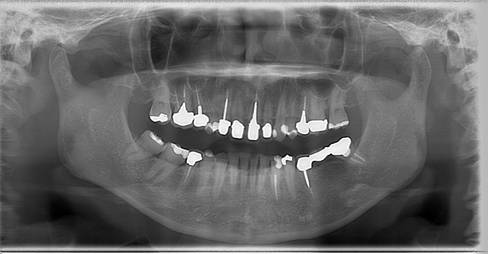

術前パノラマレントゲン写真。根の周りが黒くなり、骨がなくなっていることがわかります